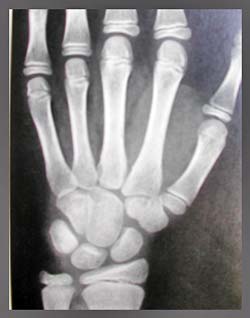

Radiografía carpal

Para la determinación de la maduración ósea (edad ósea) se realizaron radiografías carpales de la mano contralateral a la usada con mayor frecuencia.(Fig 1) Para ello se utilizó un tiempo de exposición de 1,5 segundos y una angulación vertical de 90º perpendicular al plano de proyección.

3º etapa: el examen e interpretación de las películas se realizó con luz blanca y magnificación idénticas ( 2 X). Las imágenes de la radiografía carpal fueron comparadas con otras consideradas como standars e incluidas en el Atlas Radiográfico de Desarrollo Esqueletal de Manos y Muñecas de Greulich and Pyle, 1959 (5). Las imágenes del canino inferior fueron comparadas con la Tabla de Fases de Desarrollo Dental adaptado por Haavikko, que clasifica la edad dentaria según la fase de mineralización de los elementos dentarios.